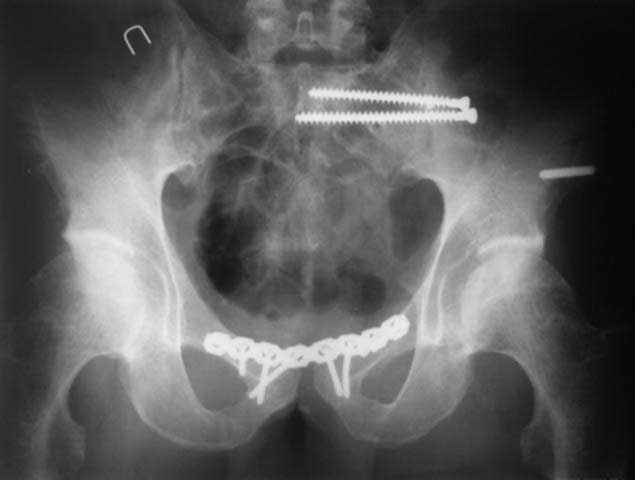

закрытое низведение правой половины таза кольцевым аппаратом (с

фиксацией задних отделов), затем проведение илиосакральных винтов,

реостеосинтез лонного сочленнения, дальнейшая фиксация в аппрате 2-3

мес. Похожий пример в приложении.